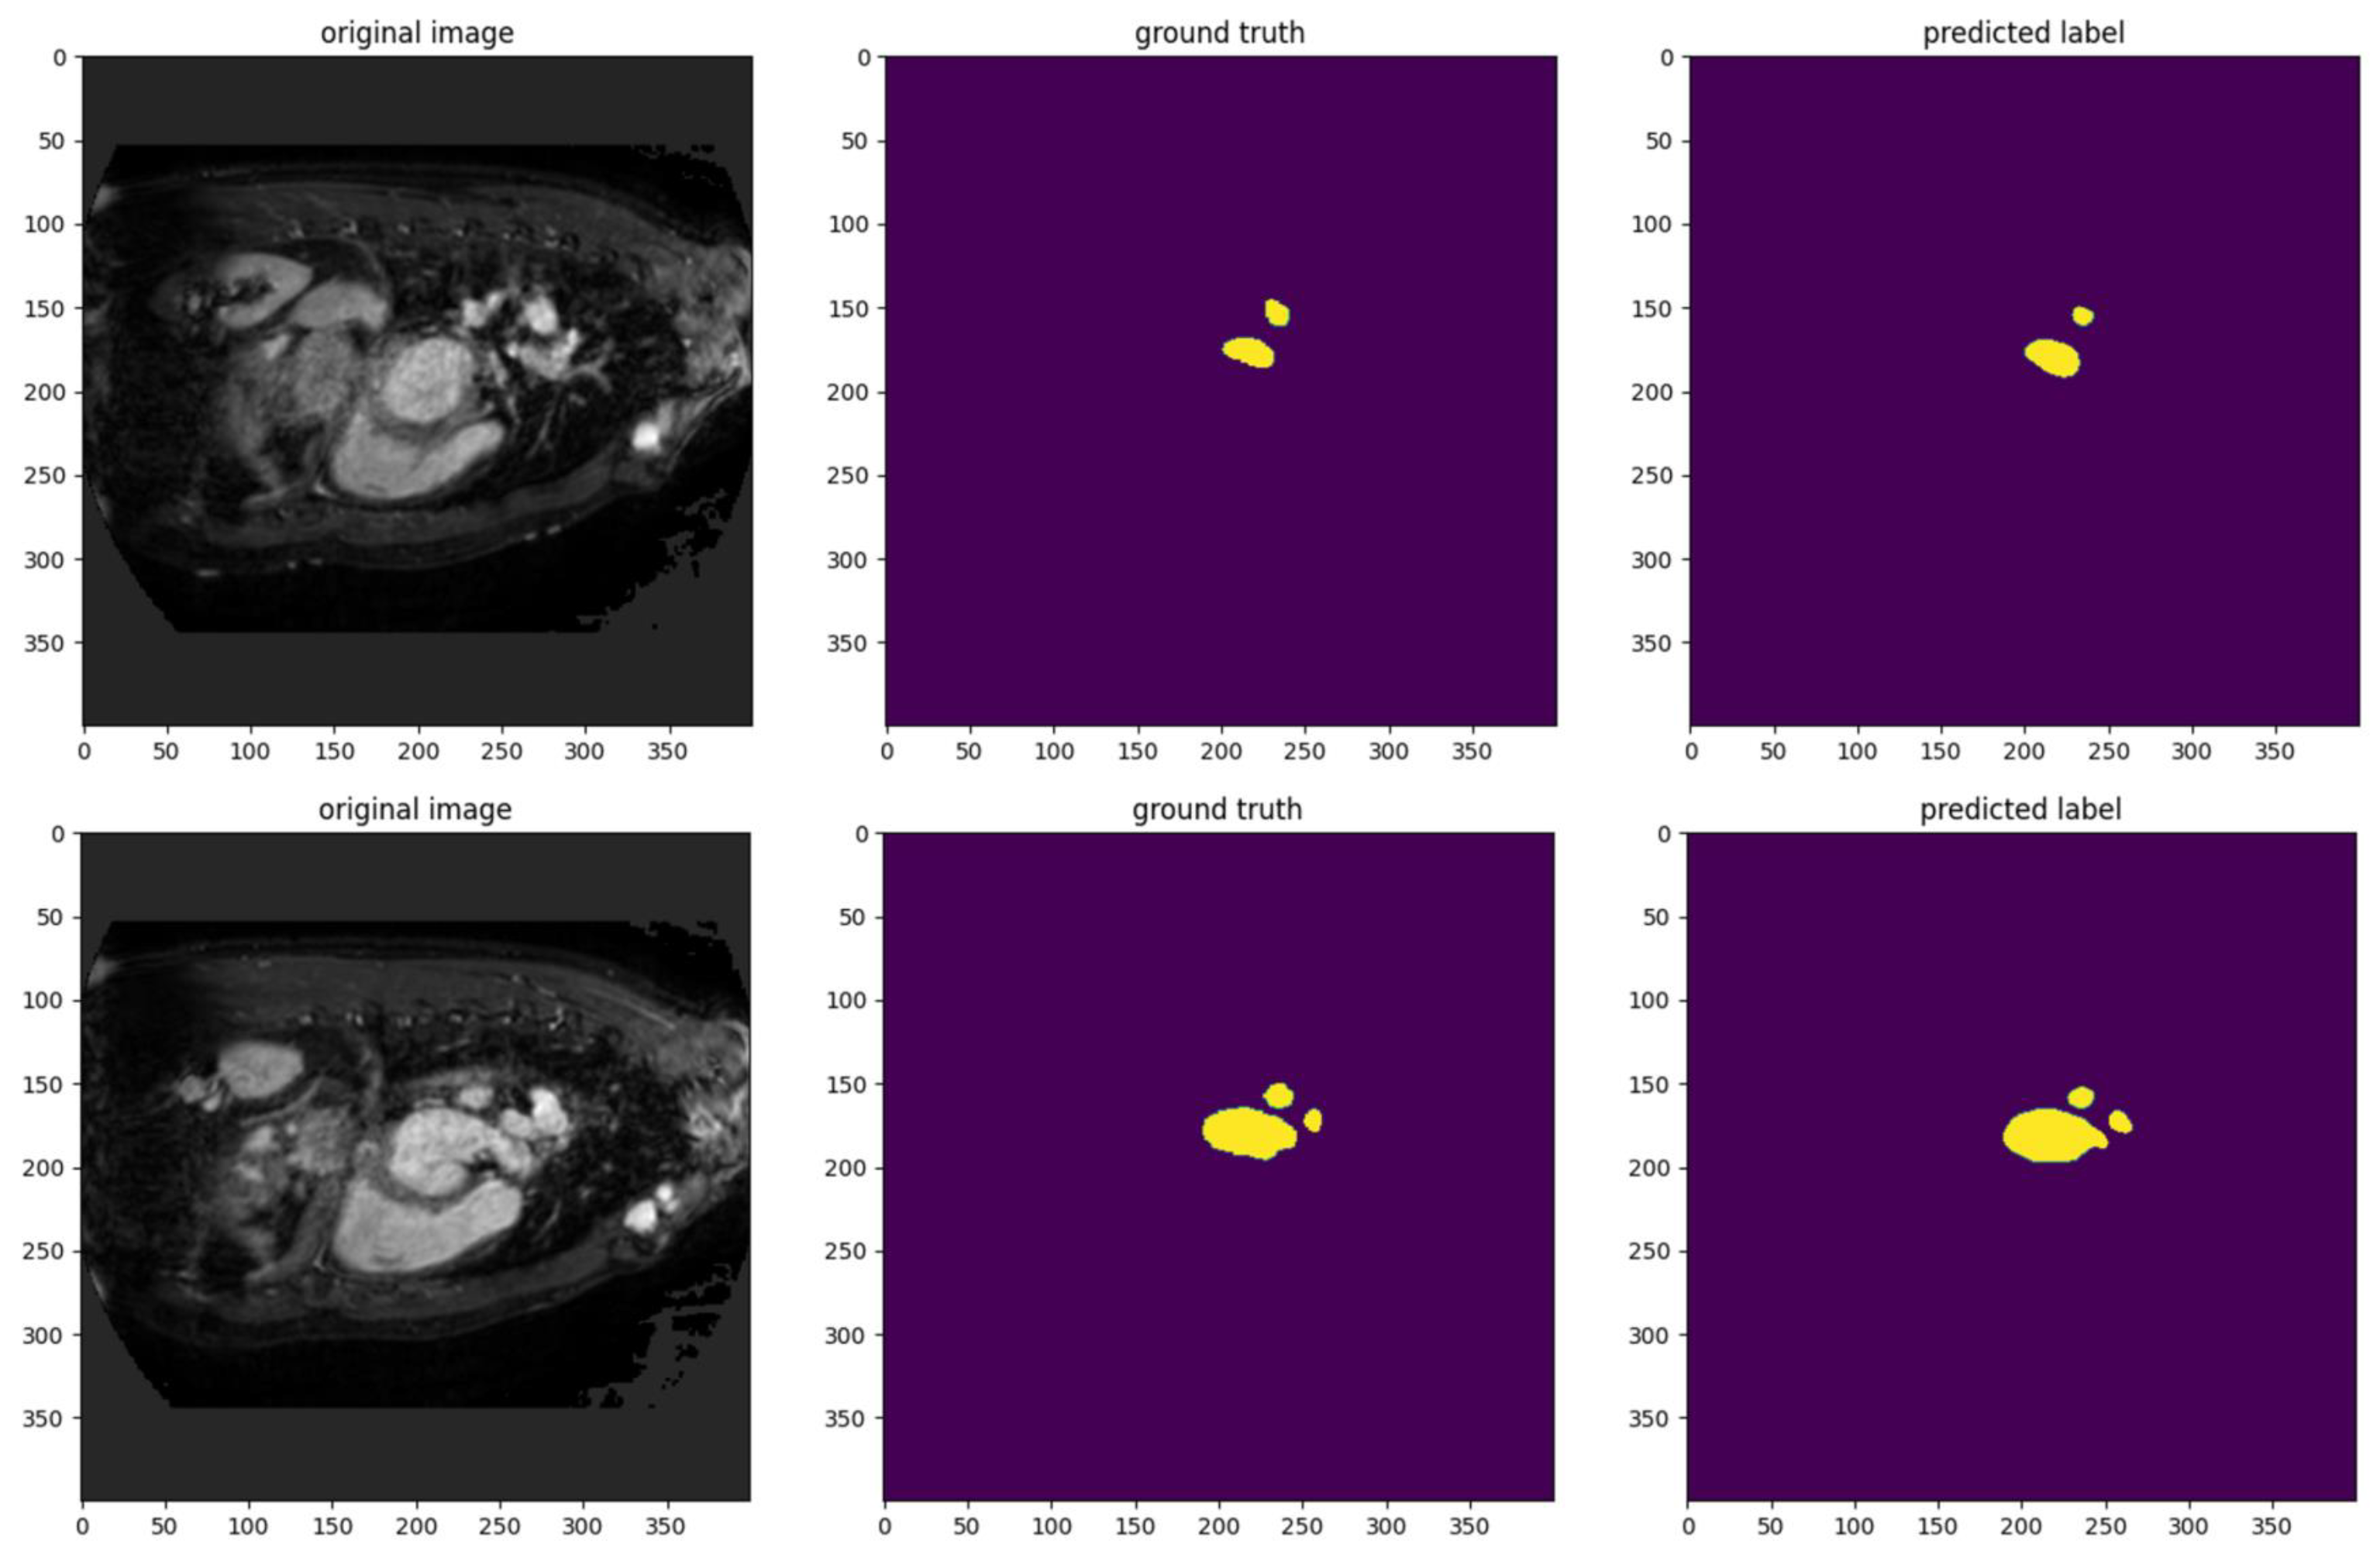

This study also performed qualitative analysis to evaluate the performance of our model against ground truth annotations. Figure 8 shows the model’s segmentation performance on sample images. Our model demonstrates a high degree of accuracy in replicating the ground truth segmentation, as the predicted labels closely align with the annotated regions. The mask regions in the predicted labels capture the shapes, sizes, and locations of the target areas in the ground truth. This indicates that the model effectively identifies and delineates the areas of interest.

Figure 8.

The visualization results of AMU-net to evaluate the performance of the model.